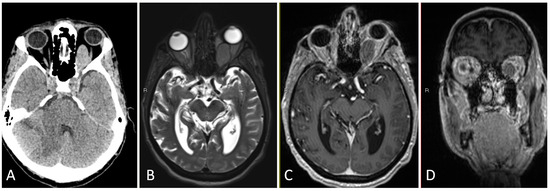

3.1.2. Illustrative Case

3.1.4. Illustrative Case